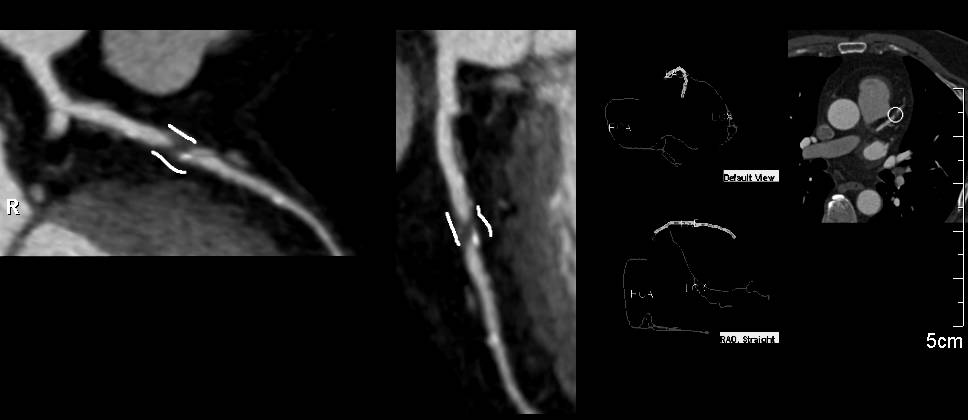

CCTA: Critical Left Anterior Descending Coronary Artery (LAD) Stenosis